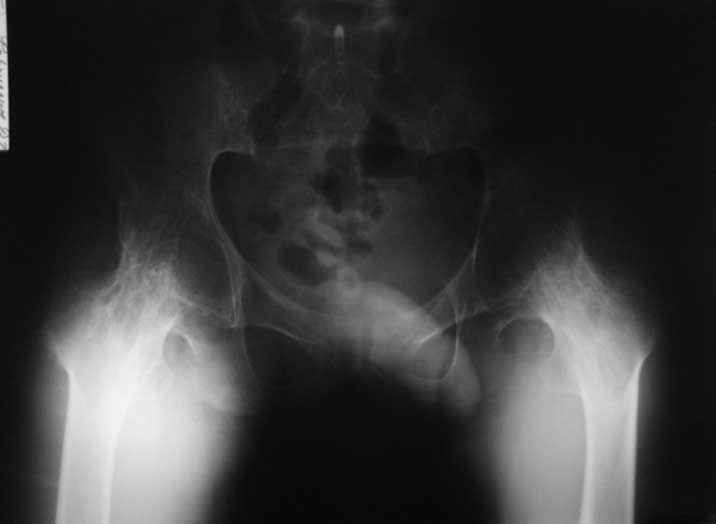

Уважаемые коллеги. пациент, страдает ревматоидным артритом с детства, ранее докладывался... костный анкилоз т/б суставов. 4 месяца назад THR левого т/б сустава, движения в т/б суставе приличные - с/р 90/5/0, движения в коленном суставе ухудшились - с/р 120/45/0. В настоящее время конечность неопорна из-за сгибательной кнтрактуры в к/с Вопросы о дальнейшей тактике лечения (пациенту 28 лет):1. рассматриваются варианты остеотомий (бедра, б/б кости), насколько это целесообразно, учитывая необходимость артротомии (остеофиты), каков может быть ожидаемый результат? варианты остеотомий (бедро или голень)?2. эндопротезирование к/с: мягкотканный дисбаланс- достаточно будет релиза капсулы и связок или мышцы тоже (учитывая разгибание в т/б после эндопротезирования и натяжение мышц на уровне колена после этого) Чего опасаться и к чему быть готовым?3. другие варианты? ссылки на литературу?собств наблюдения?С уважением Максим Агалаков